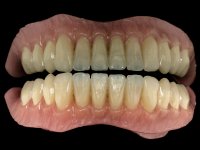

The overdentures with a metallic framework were fabricated over the bars, according to the silicone walls previously made. Before finishing the dentures, a new functional and aesthetic evaluation of the teeth was done, together with a new jet-bite registration to allow small occlusal adjustments.

The bars were finally screwed over the implants with the adequate torque and the overdentures set-in-place. Maintenance instructions were given to the patient regarding oral hygiene and overdentures insertion / removal.